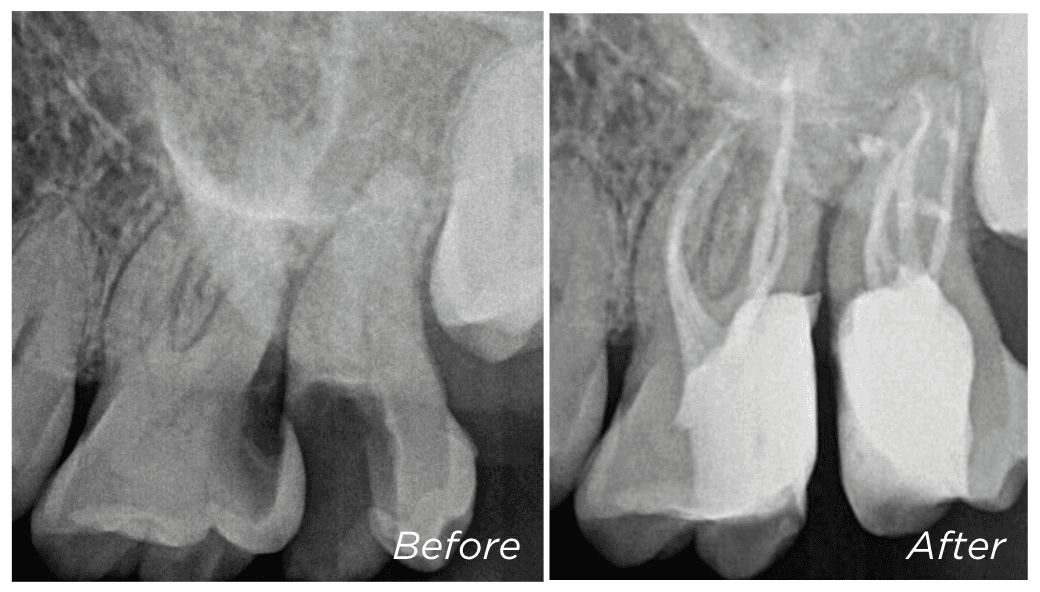

Some teeth are referred to us as “unrestorable” — meaning the decay has extended too deep to reliably place a new filling or crown. But in many cases, we’re able to save these teeth using a technique called deep margin elevation (DME).

This involves carefully removing the old filling and placing a new restoration deeper into the tooth — using special techniques to ensure it is secure and well sealed.

We won’t know if DME is possible until the old filling has been removed and we can assess how much healthy tooth remains. If we’re able to place a well-sealed restoration, the tooth may still be suitable for root canal treatment and long-term restoration.

If DME isn’t an option, surgical crown lengthening may help expose more of the tooth — this is explained in the next section.

Dr Kreena Patel is often referred teeth that others consider unsalvageable — and she will always explore every option to help preserve your natural tooth wherever possible